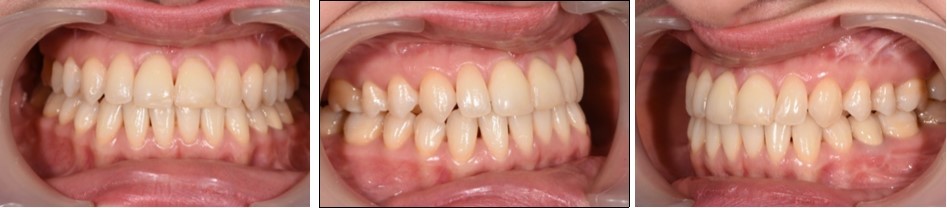

Intraoral examination revealed bilateral Angle’s class III molar relationship, class III canine relationship on the right and class I on the left, a deviated lower dental midline to the left of the patient, a visible negative tip in the right upper lateral incisor and canine, crossbite between 1.2. and 4.3 and 4.4, retroclined lower incisors, proclined upper incisors, with a 1 mm overbite and overjet . (Figure 2)

Figure 2.Initial intraoral photographs